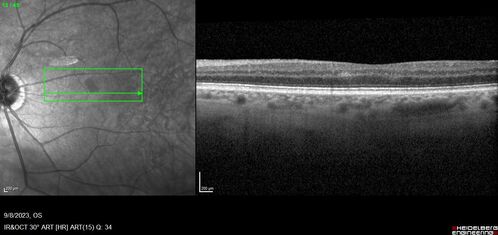

Paracentral acute middle maculopathy - isolated

83 year old man New spot in the vision yesterday left eye.

Medical Hx: Pure Hypercholesterolemia

Systemic Meds: Crestor.

VA OD: Dcc20/20

VA OS: Dcc20/20

IOP: TP: OD:19 OS:10